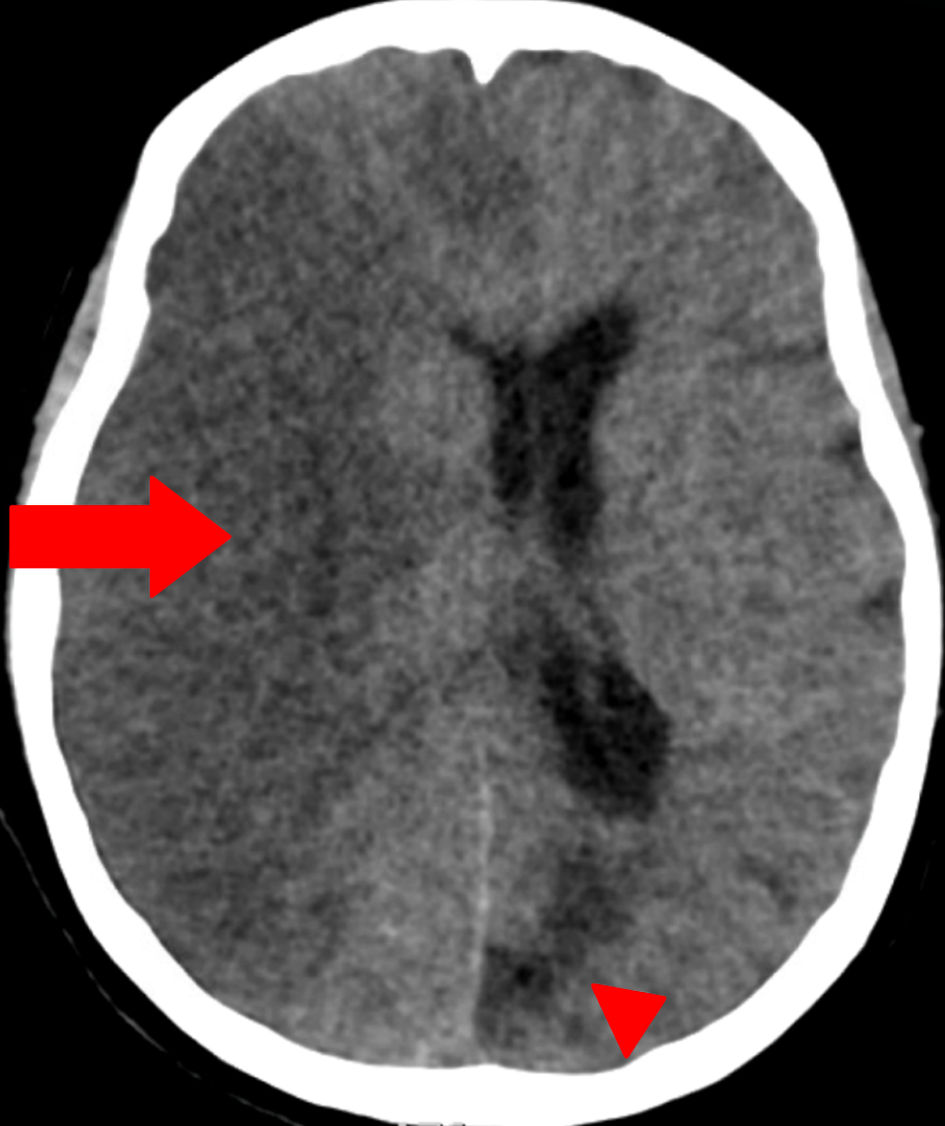

By hospital day 3, follow-up head CT demonstrated extensive right-hemispheric swelling with a progressive midline shift (7 mm to 12 mm), evolving acute ischemia in the posterior and anterolateral right frontal lobes, and diffuse cerebral edema consistent with evolving infarction, without hydrocephalus (Fig. 2). Repeat imaging with dual energy CT showed contrast in the subarachnoid space with no hemorrhage but revealed midline shift (12 mm) with progressive infarction in the right frontal and parietal lobes (Fig. 3). There was no acute hydrocephalus, but there were radiographic signs of increased intracranial pressure (ICP) (Fig. 2). Lumbar puncture was contraindicated by her coagulopathy and imaging findings. Laboratory testing showed hemoglobin 6.7 g/dL (reference 12.0 - 16.0) and hematocrit 21.6% (reference 36.0 - 46.0). Two units of cryoprecipitate were administered and post-transfusion labs showed that hemoglobin had risen to 7.3 g/dL (reference 12.0 - 16.0) and hematocrit to 23.4% (reference 36.0 - 46.0), with persistent thrombocytopenia (platelets 58 × 103/µL, reference 130 - 400) and normocytic indices (MCV 81.5 fL, reference 80.0 - 100.0). Chemistry and coagulation studies demonstrated hyperbilirubinemia (total bilirubin 4.7 mg/dL; indirect bilirubin 3.4), azotemia (blood urea nitrogen (BUN) 62 mg/dL, reference 10 - 25, creatinine 3.50 mg/dL, reference 0.70 - 1.40), and coagulopathy (prothrombin time 26.4 s reference 11.3 - 14.7, INR 2.6 reference 0.9 - 1.2). The patient’s clinical status continued to deteriorate despite maximal supportive measures, including hyperosmolar therapy (mannitol) for cerebral edema and strict blood pressure control to minimize further stroke extension. Broad rheumatologic and infectious workups (antinuclear antibody (ANA), antineutrophil cytoplasmic antibodies (ANCA), rheumatoid factor, anti-cyclic citrullinated peptide antibodies, antiphospholipid antibodies, vasculitis panel, rapid plasma reagin (RPR) for syphilis) were unremarkable. Therapeutic PLEX and methylprednisolone were initiated for TTP as it remained a leading possibility (given thrombocytopenia with microangiopathic hemolysis). Despite maximal supportive measures including ICP-directed therapy, ventilatory management, and PLEX, the patient’s neurological status did not improve. Given the extent of infarction, lack of brainstem reflexes, and poor prognosis, multidisciplinary goals-of-care discussions were held with the family. In light of irreversible neurologic injury and systemic deterioration, the decision was made to transition to comfort-focused care with withdrawal of life-sustaining therapies.

Figure 3. Dual-energy computed tomography (DECT) of the head (axial view). Red arrow indicates a large area of hypodensity involving the right cerebral hemisphere, associated with pronounced mass effect and midline shift, consistent with an extensive acute-to-subacute ischemic infarct. No subarachnoid hemorrhage is seen. Red arrowhead marks an area of chronic ischemic injury/encephalomalacia in the left occipital region, characterized by parenchymal volume loss and gliosis. The use of arrowheads differentiates chronic lesions from acute/subacute pathology.